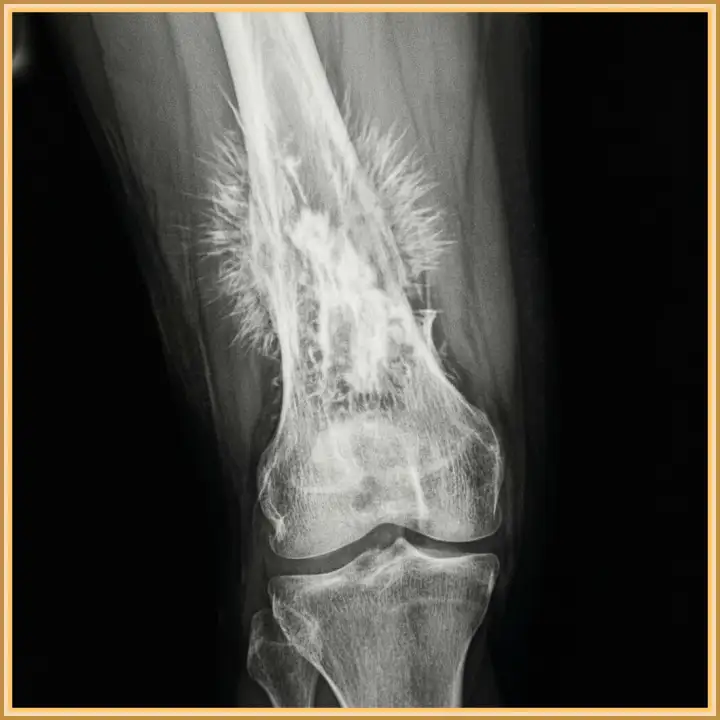

Жуткая опухоль костной ткани.

Так выглядит остеосаркома.

На снимке — кость, разрушенная остеосаркомой. Самый пугающий и одновременно крайне показательный признак здесь — так называемые спикулы, или игольчатый периостит. Видите торчащие острые «лучи», похожие на ежиные иголки? Это не случайное совпадение. Такая картина — не просто деталь, а важнейший маркер стремительного роста злокачественной опухоли, которая молниеносно врастает в соседние ткани, создавая хаотичные костные наросты.

Для специалистов по онкологии и рентгенологов подобная картинка на снимке — не просто заключение, а тревожный звоночек, требующий мгновенной реакции. Игольчатый периостит зачастую говорит о высокой злокачественности новообразования и его быстром прогрессе. Каждый потерянный день здесь может стать решающим. Это гонка на время, на кону которой — человеческая жизнь.